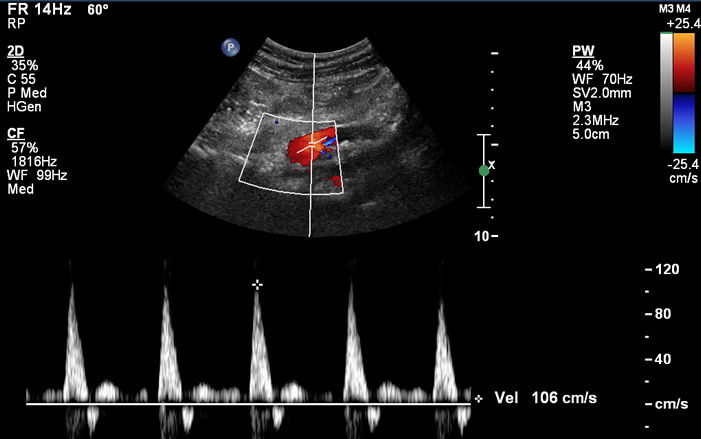

ULTRAHANG DIAGNOSZTIKA

Időpont egyeztetés a +36 30 9022 154 vagy a +36 34 473-030 telefonszámon.